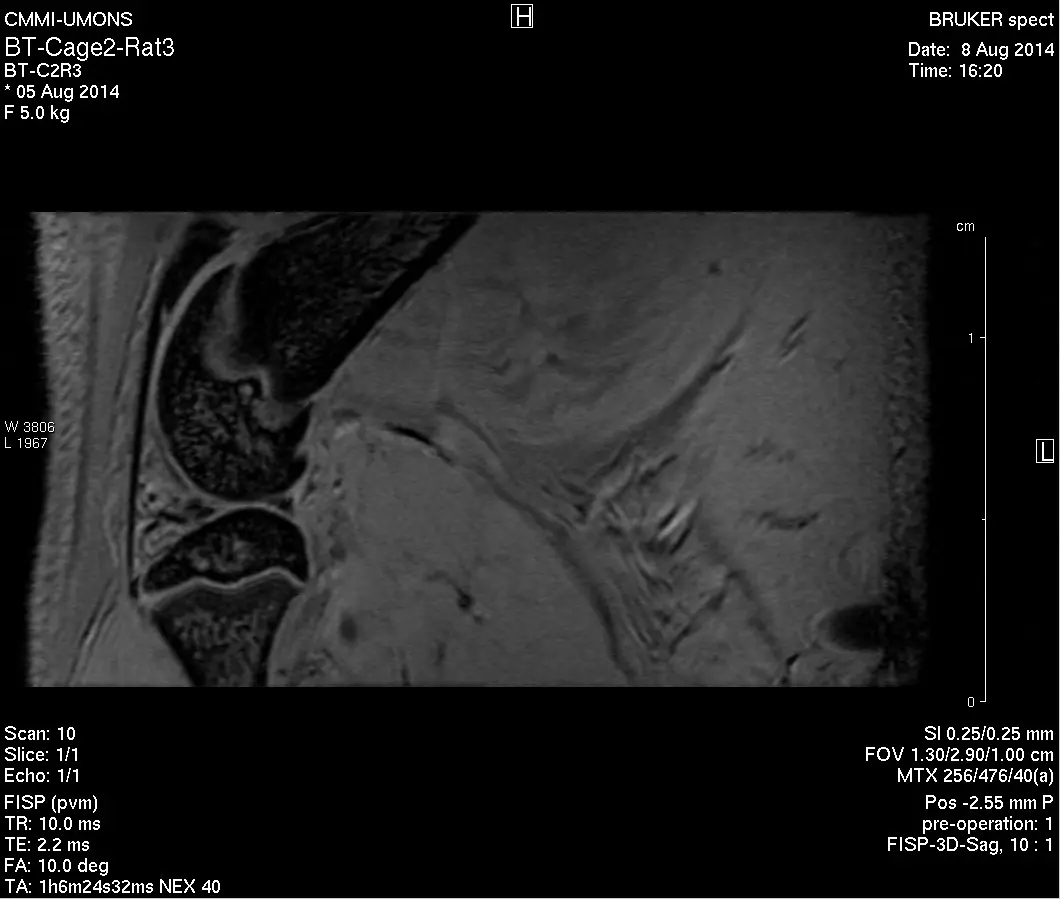

- 9.4T MRI

Bruker, Biospec 94/20, equipped with mouse head & body, rat body & surface 1H coils, 19F/1H mouse body coil, 13C/1H surface coil. - 1T MRI